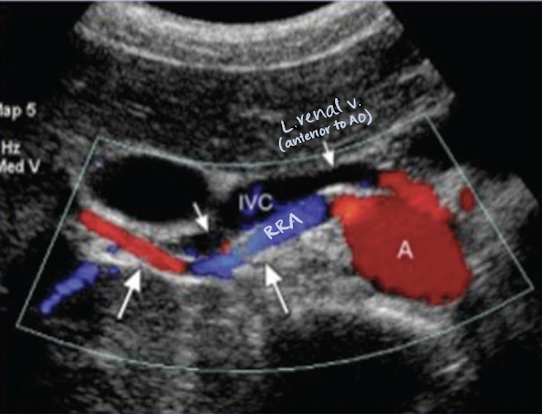

renal arteries (RRA and LRA)

inferior to SMA

courses horizontally to supply the kidneys

RRA

RRA is longer than LRA and courses posterior to IVC (goes excuse me under the IVC)

renal veins (RRV and LRV)

posterior to SMA

anterior to AO

LRV is longer than RRV